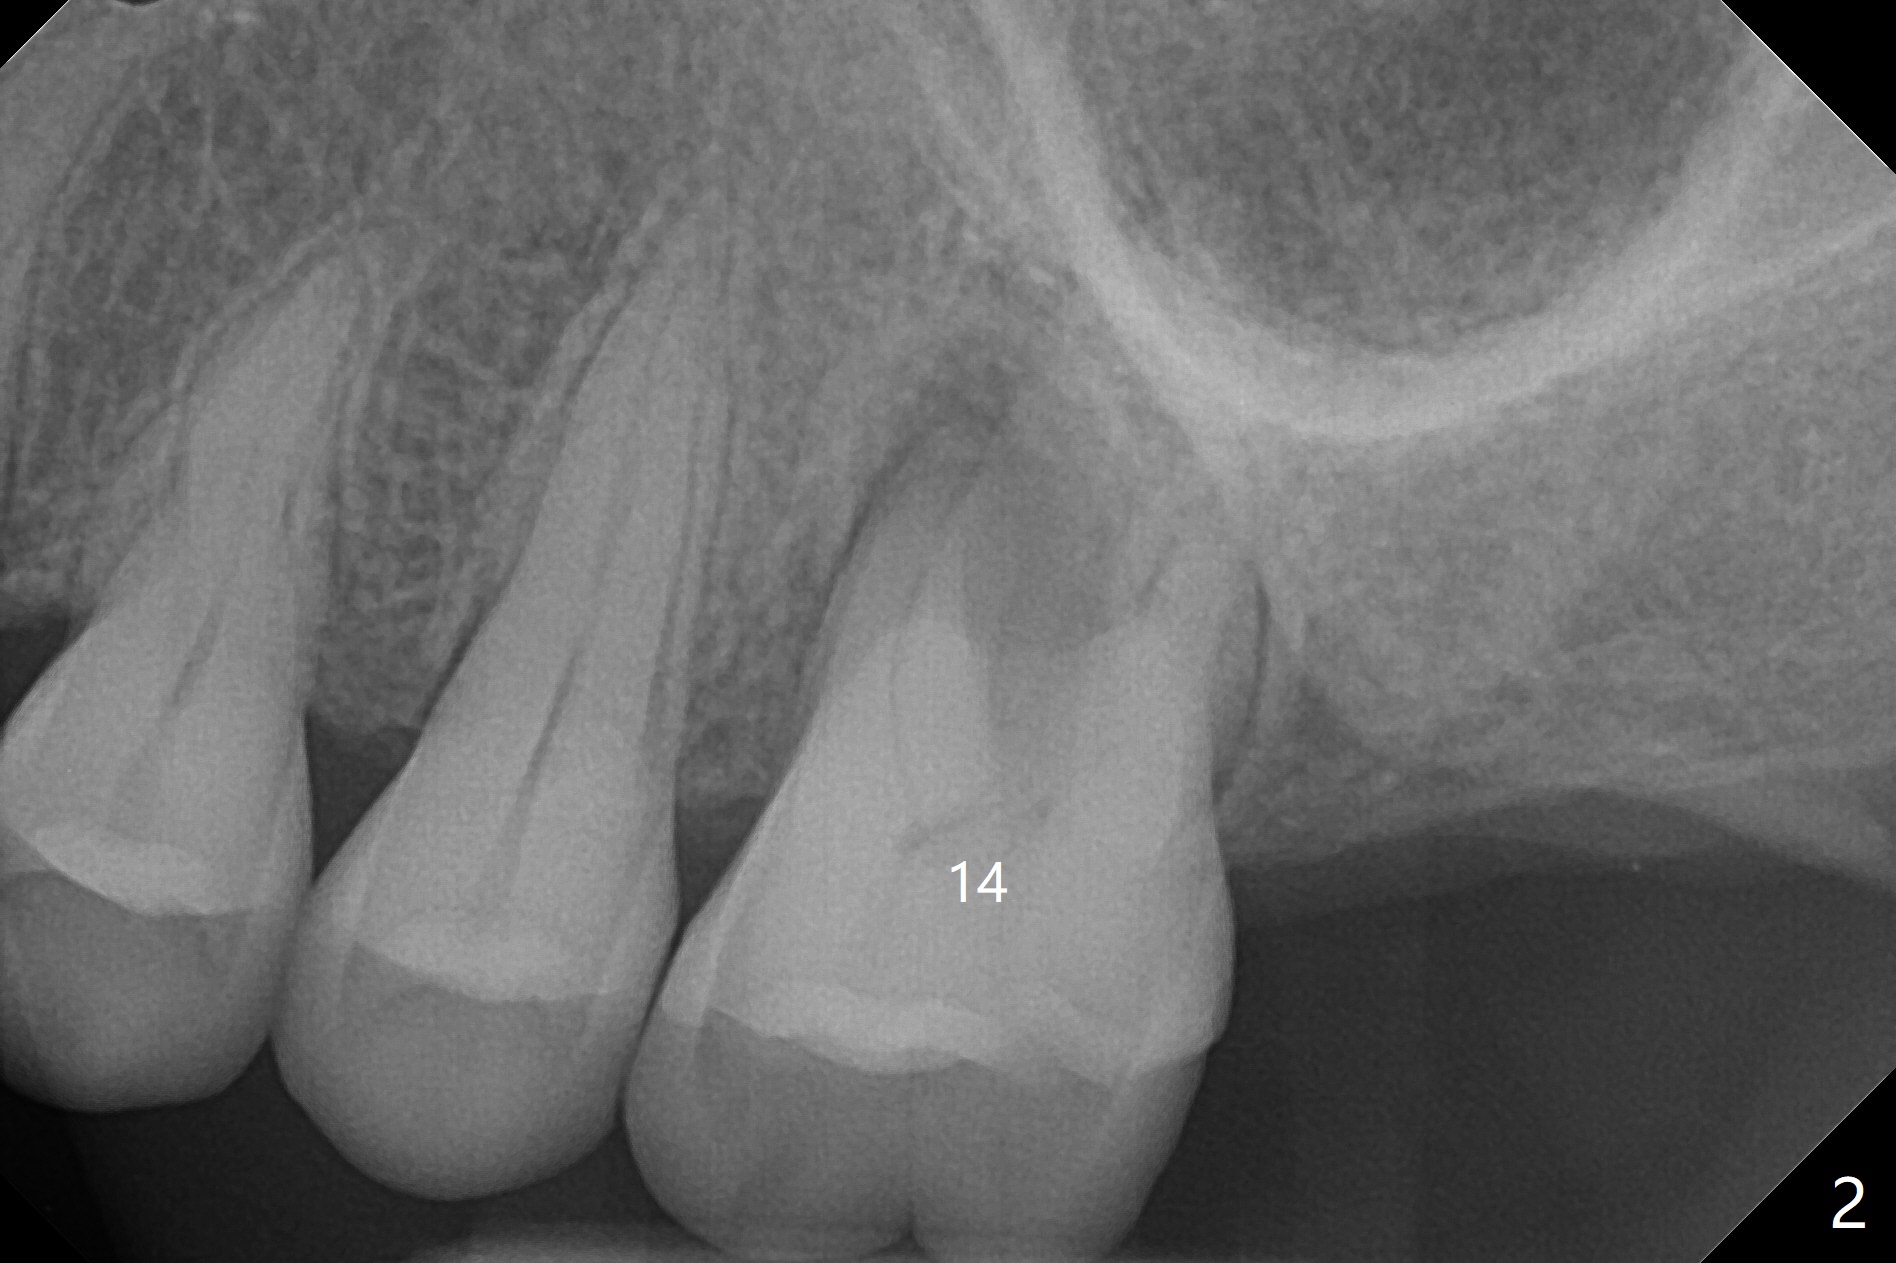

A 61-year-old woman with history of bruxism returns to clinic with chief complaint "I cannot chew bottom right. Top left has had pain and swelling before". Exam shows loose FPD at #31 (Fig.1) and necrosis of #14 (Fig.2). When the FPD is sectioned, the tooth #31 is found to have subgingival caries, filled with IRM (Fig.3). CT shows large PARL around MB and P roots of the tooth #14 (Fig.4), the fractured distal root of the tooth #19 with the low buccal plate (Fig.5) and a 5x10 mm implant being able to be placed at #30 (Fig.6). The crestal cortex (Fig.7 arrowheads) is thin in the edentulous area for several decades. The bone density is low (Fig.8, underprep). To place an implant over the pointed ridge, it should be trimmed prior to osteotomy (Fig.9). The bone loss associated with the fractured distal root is severe at #19 (Fig.10). After removal of the mesial root (Fig.11: 1), perform distal socket shield (2).